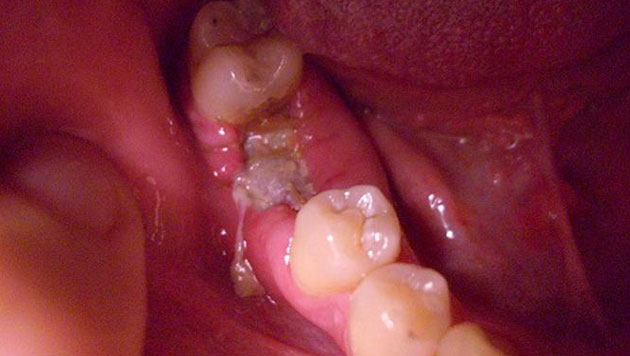

Отдавать болезненными ощущениями в скулу может даже тогда, когда имеет место обычный кариес или пульпит, периодонтит, стоматит или альвеолит, возникший вследствие удаления зуба. Ведь все органы челюстно-лицевого аппарата расположены в опасной близости друг от друга.

Хуже, когда простое стоматологическое заболевание долго оставалось невылеченным и инфекция начала распространяться дальше, дойдя до скуловой области лица. Тогда у вас уже могут болеть скулы от более серьезной патологии – остеомиелита. Заболевание поражает костную ткань челюсти, вызывая ее нагноение и некроз, сопровождается общим ухудшением самочувствия, поднимается температура тела, лицо может опухнуть и деформироваться.

«Остеомиелит верхней челюсти наблюдается во врачебной практике значительно реже, чем нижней. Тем не менее, заболевание считается очень опасным, т.к. его несвоевременное или неправильное лечение может привести к перелому челюсти, к сепсису, к поражению внутренних органов, к легочной недостаточности, флегмоне. Поэтому его необходимо лечить хирургически, дополнительно применять противовоспалительную терапию, антибиотики, лечить подвергшиеся патологическому процессу соседние органы и удалять пораженные зубы», – поясняет Цориева Э.О., терапевт, хирург.

Остеомиелит бывает разных видов: травматический, лучевой (возникает на фоне появления злокачественных раковых опухолей), гематогенный (инфекция попадает через кровь от соседних пораженных органов). Но чаще всего заболевание носит одонтогенный характер, т.е. является следствием запущенных кариеса, пульпита и других стоматологических проблем.

Частой причиной, по которой болит скула при жевании, является одонтогенная боль, связанная с болезнями зубов. К таковым относят:

- кариес;

- периодонтальный абсцесс;

- заболевания пульпы.

Обычно болезненность становится более интенсивной по ночам, имеет пульсирующий характер с выраженной локализацией в области больного зуба. Часто она возникает при употреблении горячего или холодного и протекает совместно с ноющей болью в деснах.